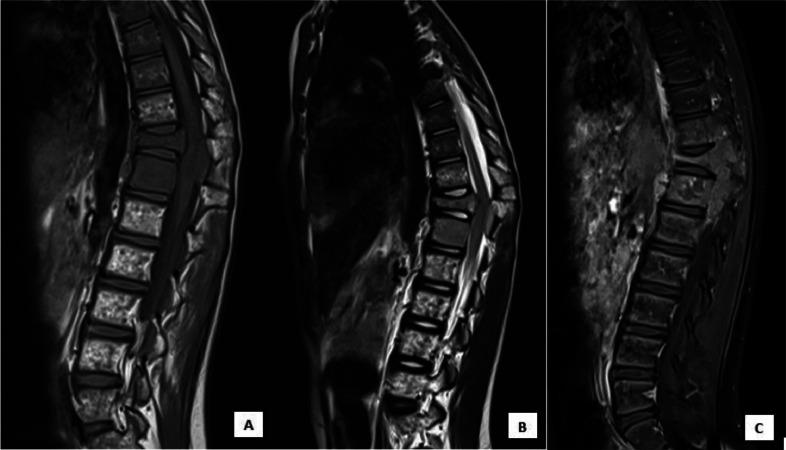

Nephroblastoma or Wilms' tumor is the most common malignant tumor of the kidney in the pediatric population. Metastasis is caused by hematogenous spread. The most common localizations in decreasing order of frequency are lymph nodes, lungs, and liver. The bone is very rarely affected. According to the literature, bone metastases have been described in the iliac bone, skull, and mandible. The vertebral localization was described in 3 cases only, the first 1 in 2009, and the 2 others in 2015 . The goal of our work is to report a very rare case of metastatic vertebral localization of a Wilms' tumor in relapse after treatment; and thus to underline the potential for vertebral and intracanal involvement in nephroblastoma.

肾母细胞瘤或威尔姆斯瘤是儿童人群中最常见的肾脏恶性肿瘤。转移是由血行播散引起的。按频率递减顺序排列,最常见的转移部位是淋巴结、肺和肝。骨骼很少受累。根据文献记载,已有髂骨、颅骨和下颌骨发生骨转移的报道。仅3例报道了椎体转移,第一例于2009年报道,另外两例于2015年报道。我们这项工作的目的是报告1例治疗后复发的威尔姆斯瘤发生椎体转移的罕见病例;从而强调肾母细胞瘤累及椎体和椎管的可能性。